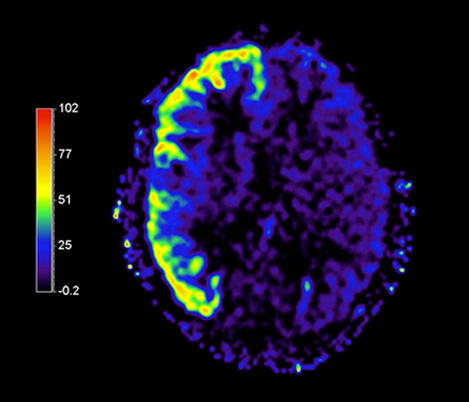

APT** and REACT**: The next steps towards non-invasive imaging strategies for pediatric MRI